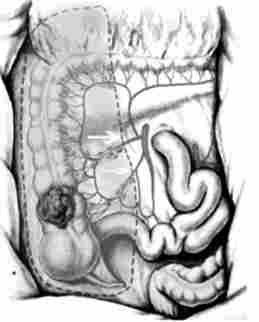

За топографії лімфогенних метастазів раку сліпої і висхідної ободової кишки для радикального видалення зон регіонарного метастазіро- вання необхідна правобічна геміколектомія з резекцією 25-30 см тонкої кишки, перев'язкою і перетином основних стовбурів a. ileocolica і a. colica dextra (Рис. 14.8). Одним блоком з кишкою видаляється забрюшін- ная клітковина з лімфатичними вузлами. При раку печінкового вигину і проксимальної третини поперечної ободової кишки видаленню підлягає лімфоколлекторов по ходу a. colica media (Рис. 14.9). Операція закінчується формуванням илеотрансверзоанастомоза (анастомозу між клубової і поперечної ободової кишкою).

Обсяг операції (правосторонньою геміколектомія) при раку сліпої і висхідної ободової кишки. Стрілками показані лігіруемие основні судини

Мал. 14.8. Обсяг операції (правосторонньою геміколектомія) при раку сліпої і висхідної ободової кишки. Стрілками показані лігіруемие основні судини

Обсяг операції (правосторонньою геміколектомія) при раку печінкового вигину ободової кишки

Мал. 14.9. Обсяг операції (правосторонньою геміколектомія) при раку печінкового вигину ободової кишки